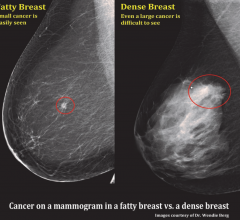

Volpara breast density measurement software provides an objective, reproducible measurement of breast density designed to improve early detection among women with dense breasts. It is used by radiologists to objectively assess density and help evaluate who might benefit from additional screening.

Lately, it seems that breast imagers cannot go a week without reading about new breast imaging research or seeing an article on breast density, the associated risk of breast cancer and the limitations of mammography. In this article, I will summarize today’s current understanding and also provide a look into what I believe the future holds for breast screening.